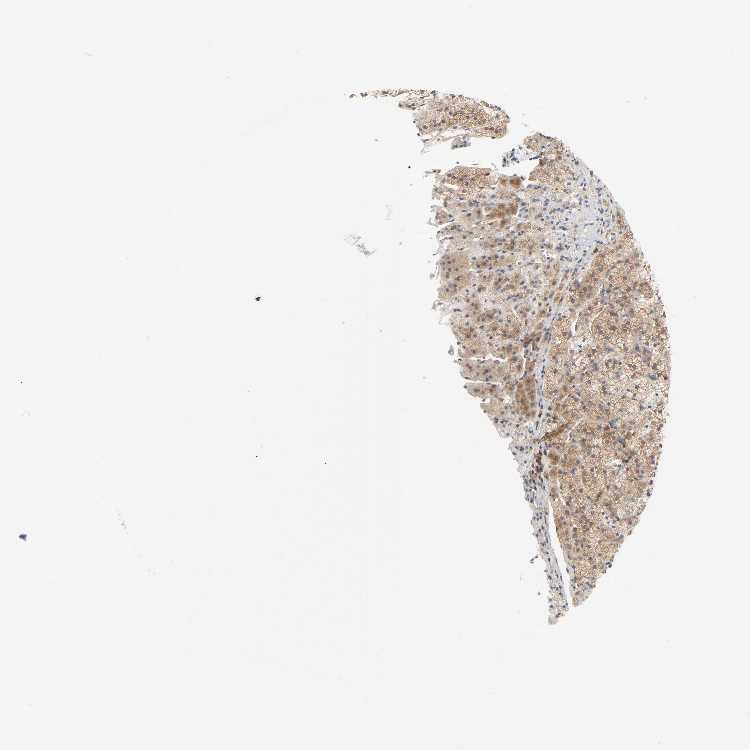

ADRENAL GLAND - Antibody stainingi

Antibody staining in the annotated cell types in the current human tissue is reported as not detected, low, medium, or high, based on conventional immunohistochemistry profiling in selected tissues. This score is based on the combination of the staining intensity and fraction of stained cells.

Each image is clickable and will lead to virtual microscopy that enables deeper exploration of all samples and also displays staining intensity scores, fraction scores and subcellular localization as well as patient and tissue information for each sample.

Antibody HPA003243Antibody HPA003445

Glandular cells MediumHigh